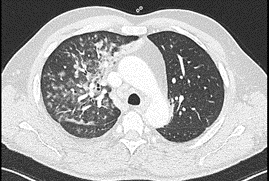

A  nasopharyngeal swab FilmArray Respiratory Panel Assay (NP FARP) was then requested: it was positive for human Metapneumovirus and the result was confirmed by repeating the test. For non responder fever and further increase of CPR (230 mg/l) and PCT (0.27 ng/ml), Levofloxacin and later Meropenem were added in the perspective of a resistant bacterial etiology.  On  the 6th hospitalization daya chest computed tomography (CT) scan was obtained (Figures 1 and 2) which demonstrated large opacities with gradient borders, distributed in the peribronchial area at the right upper lobe, middle lobe and both the lower lobes; they tended to the confluence configuring parenchymal consolidations with aerial bronchogram at the level of the cost-phrenic angle. Imaging also showed bilateral hilar and mediastinal lymphadenopathy (max diameter 3.4 x 2 cm), splenomegaly and absence of pleural effusion. Blood chemistry tests for HIV, Aspergillus antigen and galactomannan were also investigated but turned out negative. To rule out other infectious agents the patient underwent bronchoscopy with bronchoalveolar lavage (BAL) into the middle lobe. BAL provides material for various microbiological and cytological tests: Gram stain, culture, Koch’s bacillus DNA, Galactomannan, Cytomegalovirus and P. Jirovecii and immunological analysis were negative. From respiratory virus panel on BAL only human Metapneumovirus was isolated, this unique microbiological data was according to the NP FARP’s result,  thus supporting and confirming the new hypothesis of a viral pneumonia in an adult patient with probable secondary mild immunosuppression due to his hematological disease. About ten days after entering the ward, there was a gradual decrease of CPR and a progressive improvement in clinical conditions and respiratory function to allow the suspension of oxygen therapy. At the end of hospitalization, pulmonary function tests were performed and showed a restrictive syndrome (FEV1/FVC 76.2, TLC 68% and VC 79% of predicted) and mild reduction of diffusion capacity (DLCO 62% and KCO 99%), probably representing the residual functional impairment due to viral pneumonia. The patient finally suspended all therapies and at discharge was referred for a one-month follow-up visit.

Figure 2.Chest computed tomography scan of a hMPV pneumonia demostrating parenchymal consolidations with aerial bronchogram